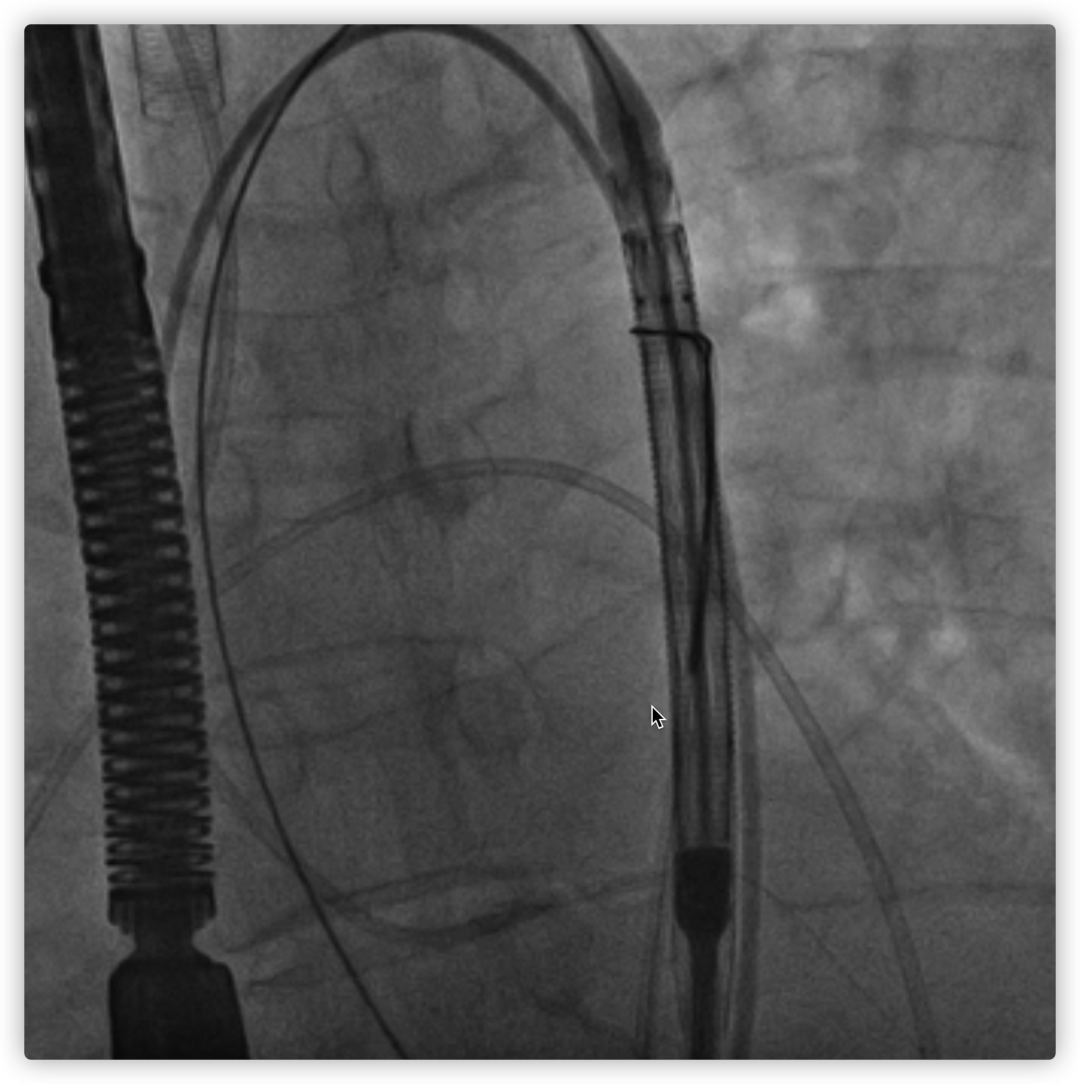

瓣膜内22mm球囊后扩张,左冠无显影

LM烟囱支架植入4.0*30mm